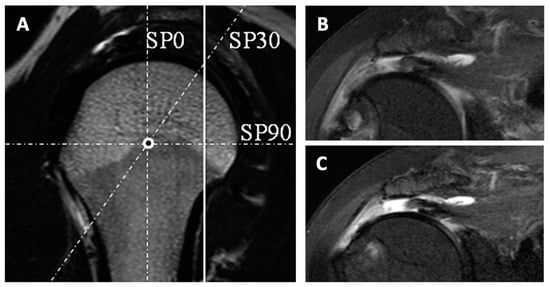

- Honda, H.; Morihara, T.; Arai, Y.; Horii, M.; Ito, H.; Furukawa, R.; Kida, Y.; Sukenari, T.; Ikoma, K.; Oda, R.; et al. Clinical application of radial magnetic resonance imaging for evaluation of rotator cuff tear. Orthop. Traumatol. Surg. Res. 2015, 101, 715–719. [Google Scholar] [CrossRef] [PubMed]

- Matsushita, R.; Yokoya, S.; Negi, H.; Matsubara, N.; Akiyama, Y.; Adachi, N. Evaluation of subscapularis tendon tears of the anterosuperior aspect using radial-sequence magnetic resonance imaging. JSES Int. 2021, 6, 97–103. [Google Scholar] [CrossRef]